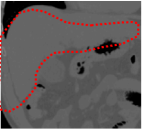

An example of CT/CBCT and MR/CBCT registration results are shown in figures 3 and 4, respectively. For both cases, the CBCT image (first column) was acquired intra-operatively after needle insertions and was employed as a reference for image registration. The pre-operative image is displayed before registration (second column), after PM-EA (third column) and after PM-EA+Evo (fourth column). The occurrence of patch shifts is reported for each spatial direction in panels (m–o): for each histogram, the shift with maximal occurrence is shown by the red dashed line. For panels (a–l), a ROI — manually defined on the CBCT image/encompassing the liver — is shown using red dash lines. Our visualization shows an improved correspondence of the contour of the liver with the manually defined liver boundary when the PM-EA solution is employed (see 3(c,g,k) and 4(c,g,k)). Moreover, an even better correspondence of the contour is observable using the PM-EA+Evo solution (see 3(d,h,l) and 4(d,h,l)).

Trans.

[X-Y]

CBCT

(a)

CT / No registration

(b)

CT / PM-EA

(c)

CT / PM-EA+Evo

(d)

Sag.

[X-Z]

(e)

(f)

(g)

(h)

Cor.

[Y-Z]

(i)

(j)

(k)

(l)

(m)

(n)

(o)